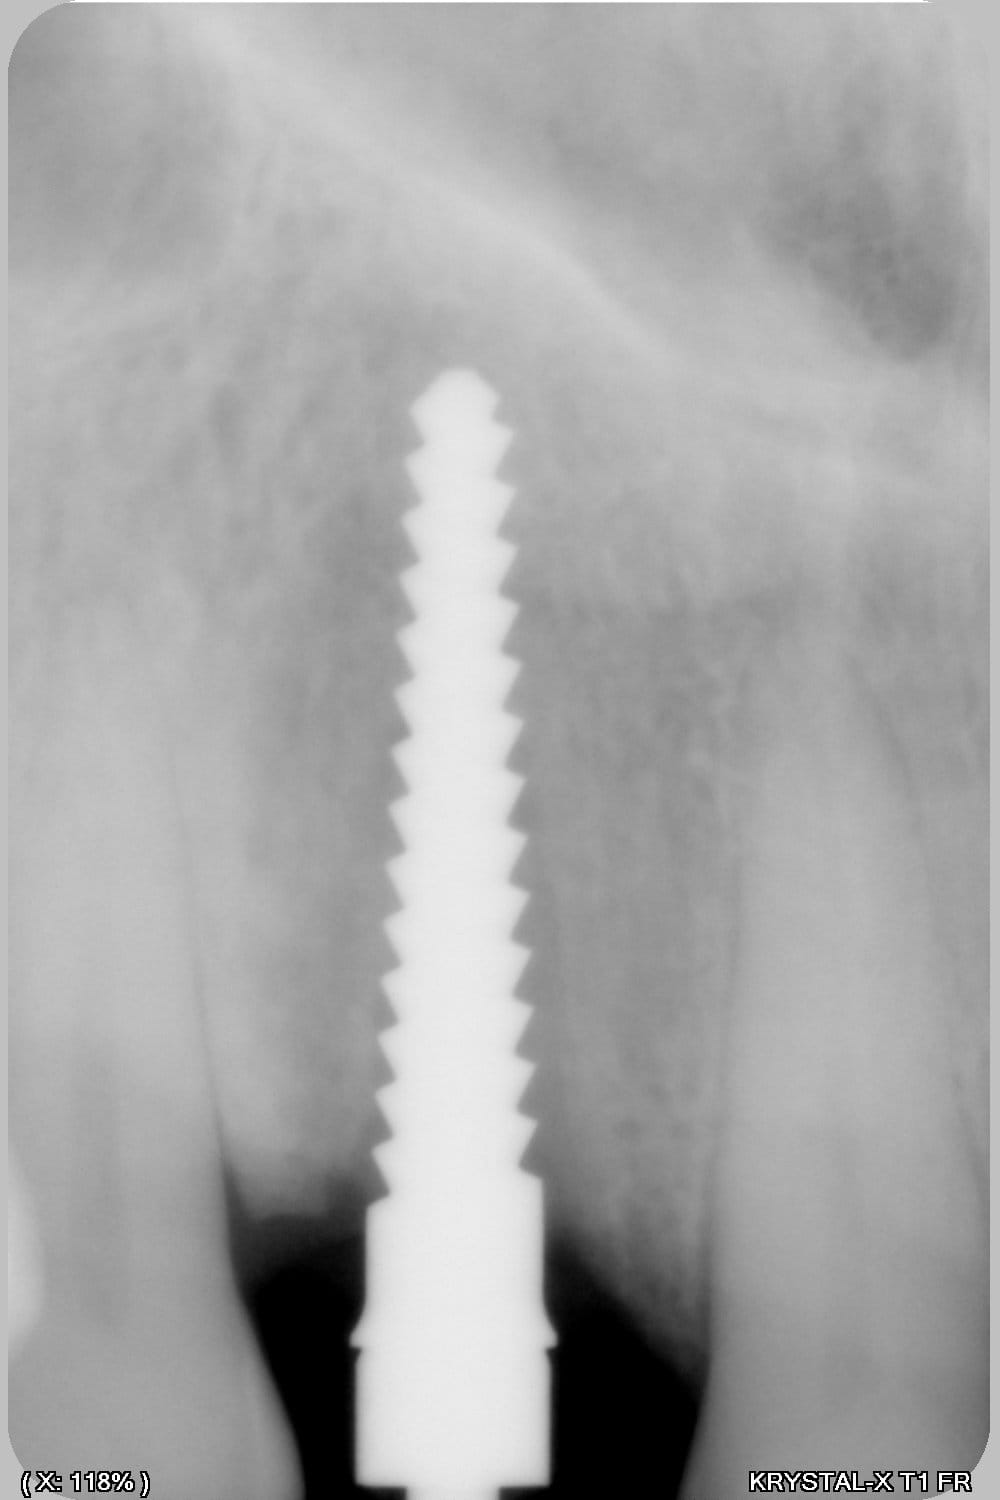

Thomas, tu as un plan pour guider dans un cas comme ça?

ou comment remplacer 12 avec soucis vestibulaire, par un implant, sans greffe, sans ROG, juste avec les mimines....?

Et bien pas de cone beam, pas de scanner,pas de panoramique...pour ne pas irradier l'os...et franchement je ne vois pas en quoi un guide me servirait dans un cas comme ça.